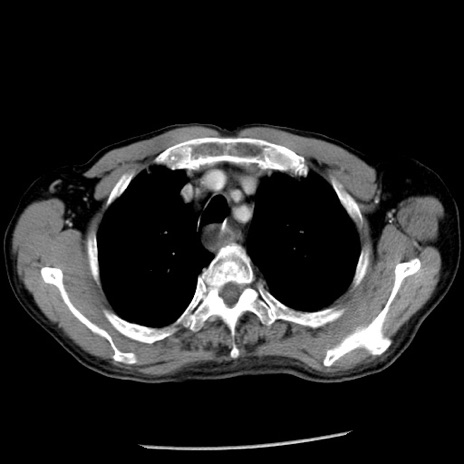

症例26(横断像)

【症例】80歳代男性

【主訴】嘔吐

【現病歴】昨晩2回嘔吐あり、今朝になっても嘔吐あり。来院。

【既往歴】胃潰瘍

【身体所見】意識清明、BT 37.6℃、BP 166/95mmHg、HR 100bpm、SpO2 97%、腹部:平坦・軟、腸蠕動音聴取良好、圧痛なし。

【データ】WBC 21900、CRP 1.46